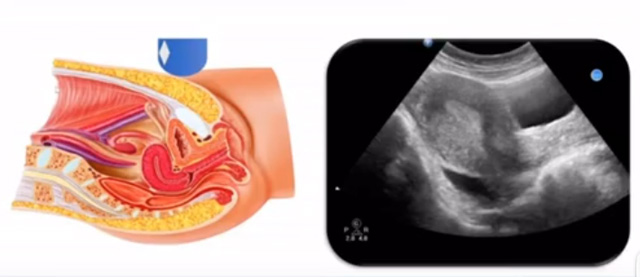

女性生殖系統(tǒng)包括內(nèi)、外生殖器官及其相關(guān)組織以及鄰近器官,其中內(nèi)生殖器是我們超聲檢查的主要對象。那么內(nèi)生殖器包括陰道、子宮還有輸卵管及卵巢。輸卵管及卵巢稱為子宮附件。子宮是倒置梨形,但是它是空腔厚壁肌性器官。它的正常值在育齡婦女。超聲探頭放在貼近腹壁盆腔上面位置,來看這個子宮在超聲上面的表現(xiàn)。從輪廓上來講,和示意圖是一樣的。這就是在超聲上面顯示的一個子宮的圖片。子宮在不同的時期與子宮頸的比例。成年婦女指的是育齡婦女為2:1子宮體是比較大的,嬰兒期為1:2說明宮頸比較大,絕經(jīng)期1:1。所以我們在看到子宮圖時候可以根據(jù)宮體宮頸比例大致可以推測屬于哪個時期的婦女。另外還可以根據(jù)比例大小來推斷是一個正常子宮還是異常子宮。

子宮從外到內(nèi),漿膜層、肌層、粘膜層。宮體部宮頸為梭形結(jié)構(gòu)。宮腔為上寬下窄的三角形,連接為峽部。子宮有什么功能呢?月經(jīng)血產(chǎn)生跟排出通道,精子運行通道受精作用。囊胚著床及胎兒發(fā)育、生長的場所。分娩時產(chǎn)生宮縮使胎兒、胎盤娩出。未孕的子宮是很小的,已孕子宮就非常大,平均胎兒都有6斤重。所以這個后壁就體現(xiàn)出來。輸卵管由子宮角部向外延伸,為一對細長而彎曲的管道,呈管狀中空結(jié)構(gòu),大概長度是8-14厘米,粗1-4毫米,它的下方為卵巢和闊韌帶。間質(zhì)部是厚一點的,峽部是比較窄的地方,壺腹部,漏斗部。正常情況下,輸卵管在普通超聲DR難以顯示。